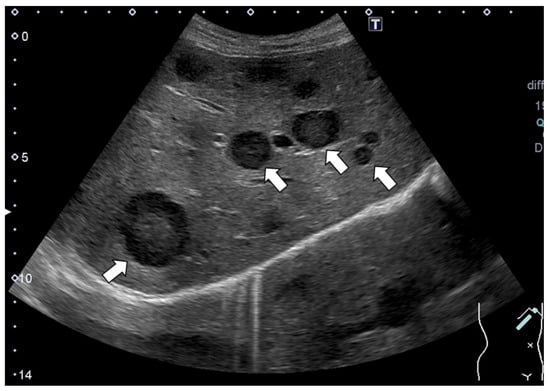

Laboratory examinations (Table 1) showed mild elevation of the serum aspartate aminotransferase and C-reactive protein (CRP) levels. The peripheral blood data, including the white blood cell count and platelet count, and the prothrombin time were found to be within the normal range. Tumor markers, such as carcinoembryonic antigen (CEA), carbohydrate antigen 19-9 (CA19-9), α-fetoprotein (AFP) and protein induced by vitamin K absence or antagonist-II (PIVKA-II), were within the normal ranges. Contrast-enhanced computed tomography (CE-CT) showed low-attenuation areas with mild peripheral enhancement at the arterial and portal phase (Figure 2), suggesting the development of metastatic liver tumors. However, no primary tumor candidate was found on the CE-CT. Esophagogastroduodenoscopy and colonoscopy did not reveal any malignant disease. In addition, despite the presence of suspected metastatic tumors on the US and CT, 18F-fluorodeoxyglucose positron emission tomography with CT (FDG-PET/CT) showed no significant uptake in the tumors (Figure 3).

Figure 2. (a) Plain CT. Multiple low-attenuation areas were detected; (b,c) contrast-enhanced CT revealed multiple low-attenuation areas with mild peripheral enhancements at the arterial (b) and portal phases (c). A typical tumor is shown with an arrow in each panel.

In our case, CE-CT showed low-attenuation areas in the center of the tumors (Figure 2). However, at the early vascular phase of CEUS, the tumors were shown as very slight hypoenhancement with some hypervascular parts. These CEUS findings were inconsistent with those of metastatic liver tumors, which have internal necrosis. Malignant lesions reportedly show a high intensity on DWI and hypo-values on ADC because of their high cell density [24,25]. Regarding the MRI findings in our case, the DWI showed high-intensity lesions; however, high values were observed on the ADC maps. In addition, the FDG-PET showed a normal standardized uptake value for the tumors. These results were atypical for metastatic tumors.

Despite the presence of findings suggestive of metastatic tumors (Figure 1 and Figure 2), we assessed several different types of clinical data available, such as different imaging techniques, and ultimately concluded that the tumors were benign. Thus, it is quite important to make a diagnosis by combining various imaging findings and considering the patient’s background and clinical course.